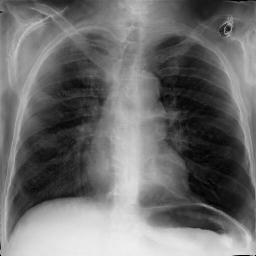

Fig. 3: Anonymization results. Real images XRX_{R} randomly selected from the training, validation, and test sets are displayed in the first column. The corresponding reconstructed images X^R\hat{X}_{R} are displayed in the second column. The anonymized images XAX_{A} are displayed in the last three columns.

Qualitative Results The visualization results are shown in Fig. 3. In this figure, the anonymized images optimized using only the utility loss ut\mathcal{L}_{ut} (column 3) exhibit greater visual similarity to their real counterparts (column 1), while those optimized using only the identity loss id\mathcal{L}_{id} (column 4) appear more distinct from their originals. Additionally, the anonymized images optimized with both the ut\mathcal{L}_{ut} and the id\mathcal{L}_{id} (column 5) strike a balance, appearing more realistic by simultaneously considering both identity removal and utility preservation.